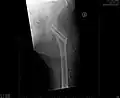

So genannte nichtdislozierte (also unverschobene) bzw. eingestauchte mediale Schenkelhalsfrakturen mit flachem Frakturneigungswinkel werden häufig mittels so genannter Zugschrauben behandelt (siehe Abbildung). Es handelt sich um hohle Schrauben, die über zuvor eingebrachte Führungsdrähte geschraubt werden (Lochschrauben). Bei jüngeren Patienten versucht man in der Regel, den Oberschenkelkopf zu erhalten. Auch hierzu werden Schrauben verwendet.[12]

- Zugschraubenosteosynthese bei einer medialen Fraktur. Behandlung einer nicht dislozierten medialen Schenkelhalsfraktur bei einer 92-jährigen Patientin.

-

Aufnahme vor der OP. a.p.-Aufnahme. Die Fraktur ist mit einem Pfeil markiert. -

Seitliche Aufnahme. Die Fraktur ist mit einem Pfeil markiert. -

Nach OP mit Zugschrauben, a.p.-Aufnahme. Man sieht die noch liegende Redondrainage. -

Seitliche Aufnahme.